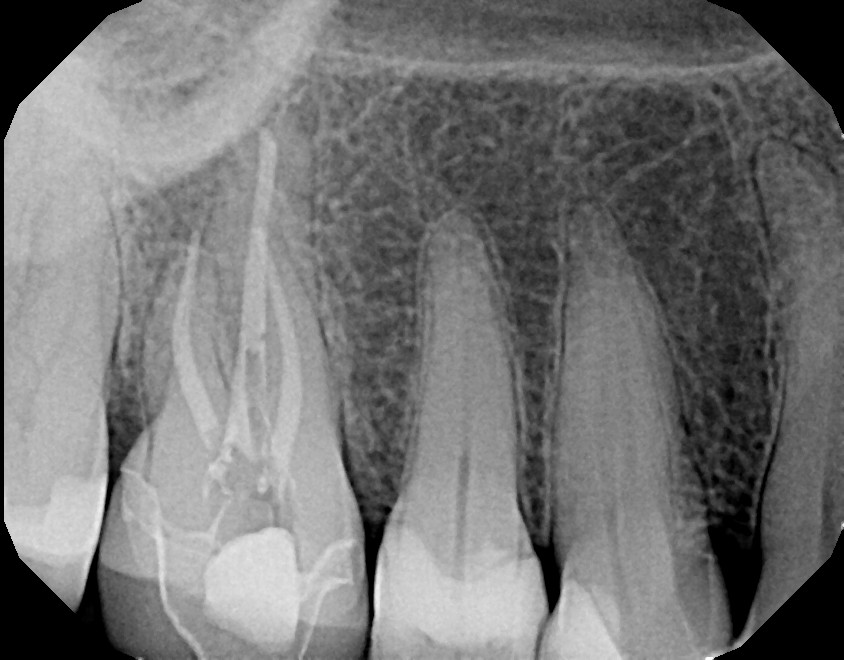

This is a first maxillary molar (tooth #3) that over time required a crown due to a large failing filling. On average, fillings last 5-8 years depending on the size and type of filling with proper oral hygiene, including daily flossing. This patient was advised of possible sensitivity that can occur after crown preparation. Prior to final/permanent crown cementation, tooth #3 became extremely sensitive to hot, cold, and bite and required root canal therapy. With patient education and referral to an endodontist, the final crown was not cemented on prior to root canal therapy. This avoided additional, unnecessary steps. Always ask your dentist/endodontist questions if you feel something doesn't feel right with your teeth, especially after dental work.